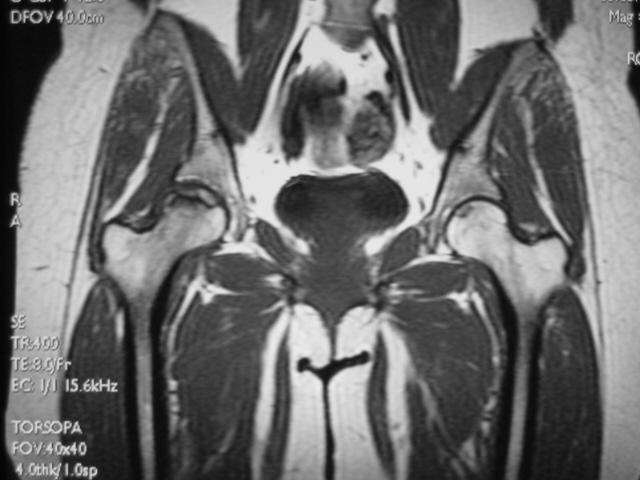

MRI诊断

MRI扫描技术

患者取仰卧位,扫描范围自髋臼上3cm至股骨粗隆下。

层厚5mm,层间距1mm连续扫描。

选择自旋回波SE序列T1WI、T2WI及STIR冠状面扫描,横轴位T1W扫描。